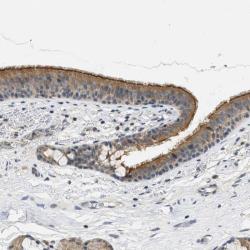

- Immunohistochemical staining of human bronchus shows moderate cytoplasmic positivity in respiratory epithelial cells. A strong membranous staining was also noted.

- Staining pattern partly consistent with experimental and/or bioinformatic data.